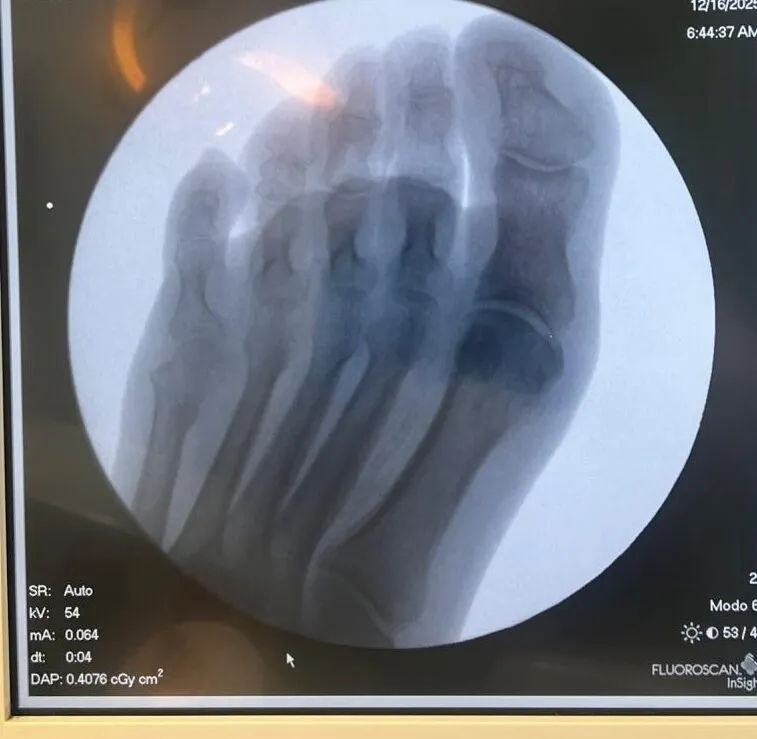

Lo que encontramos: Durante la exploración observamos una úlcera interdigital de tamaño importante, con la piel muy macerada alrededor, enrojecimiento e inflamación que se extendían al dorso del pie. Dada la intensidad del dolor y el perfil del paciente, realizamos una radiografía que reveló alteración ósea asociada.

Esto no era una simple rozadura. Lo que parecía una herida menor tenía afectación en profundidad.